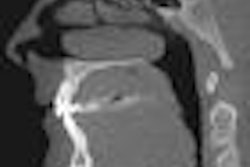

While lateral radiographs provide "reliable evaluation" of the quantity of bone in preoperative diagnosis of palatal implants, additional 3D imaging is only required in rare cases of borderline dimensions, according to a new study in Clinical Implant Dentistry and Related Research (February 3, 2010).

Researchers from the department of orthodontics at the University Medical Center Mainz set out to evaluate the diagnostic value of lateral radiographs in preoperative diagnostics for orthodontic anchorage implants, and whether CT or cone-beam CT (CBCT) are necessary as additional preoperative diagnostic tools in such cases.

A total of 105 patients were screened during the observation period. Fourteen patients opted for alternative treatment, leaving 91 patients for final evaluation. In 89 patients (98%), the lateral radiographs showed sufficient bone in the vertical dimension. In all of these cases, the availability of sufficient bone was confirmed intraoperatively.

"Lateral radiographs permit correct and reliable evaluation of the quantity of bone in preoperative diagnosis of palatal implants," the researchers concluded. "Additional imaging (CT or CBCT) is only required in rare cases of borderline dimensions."